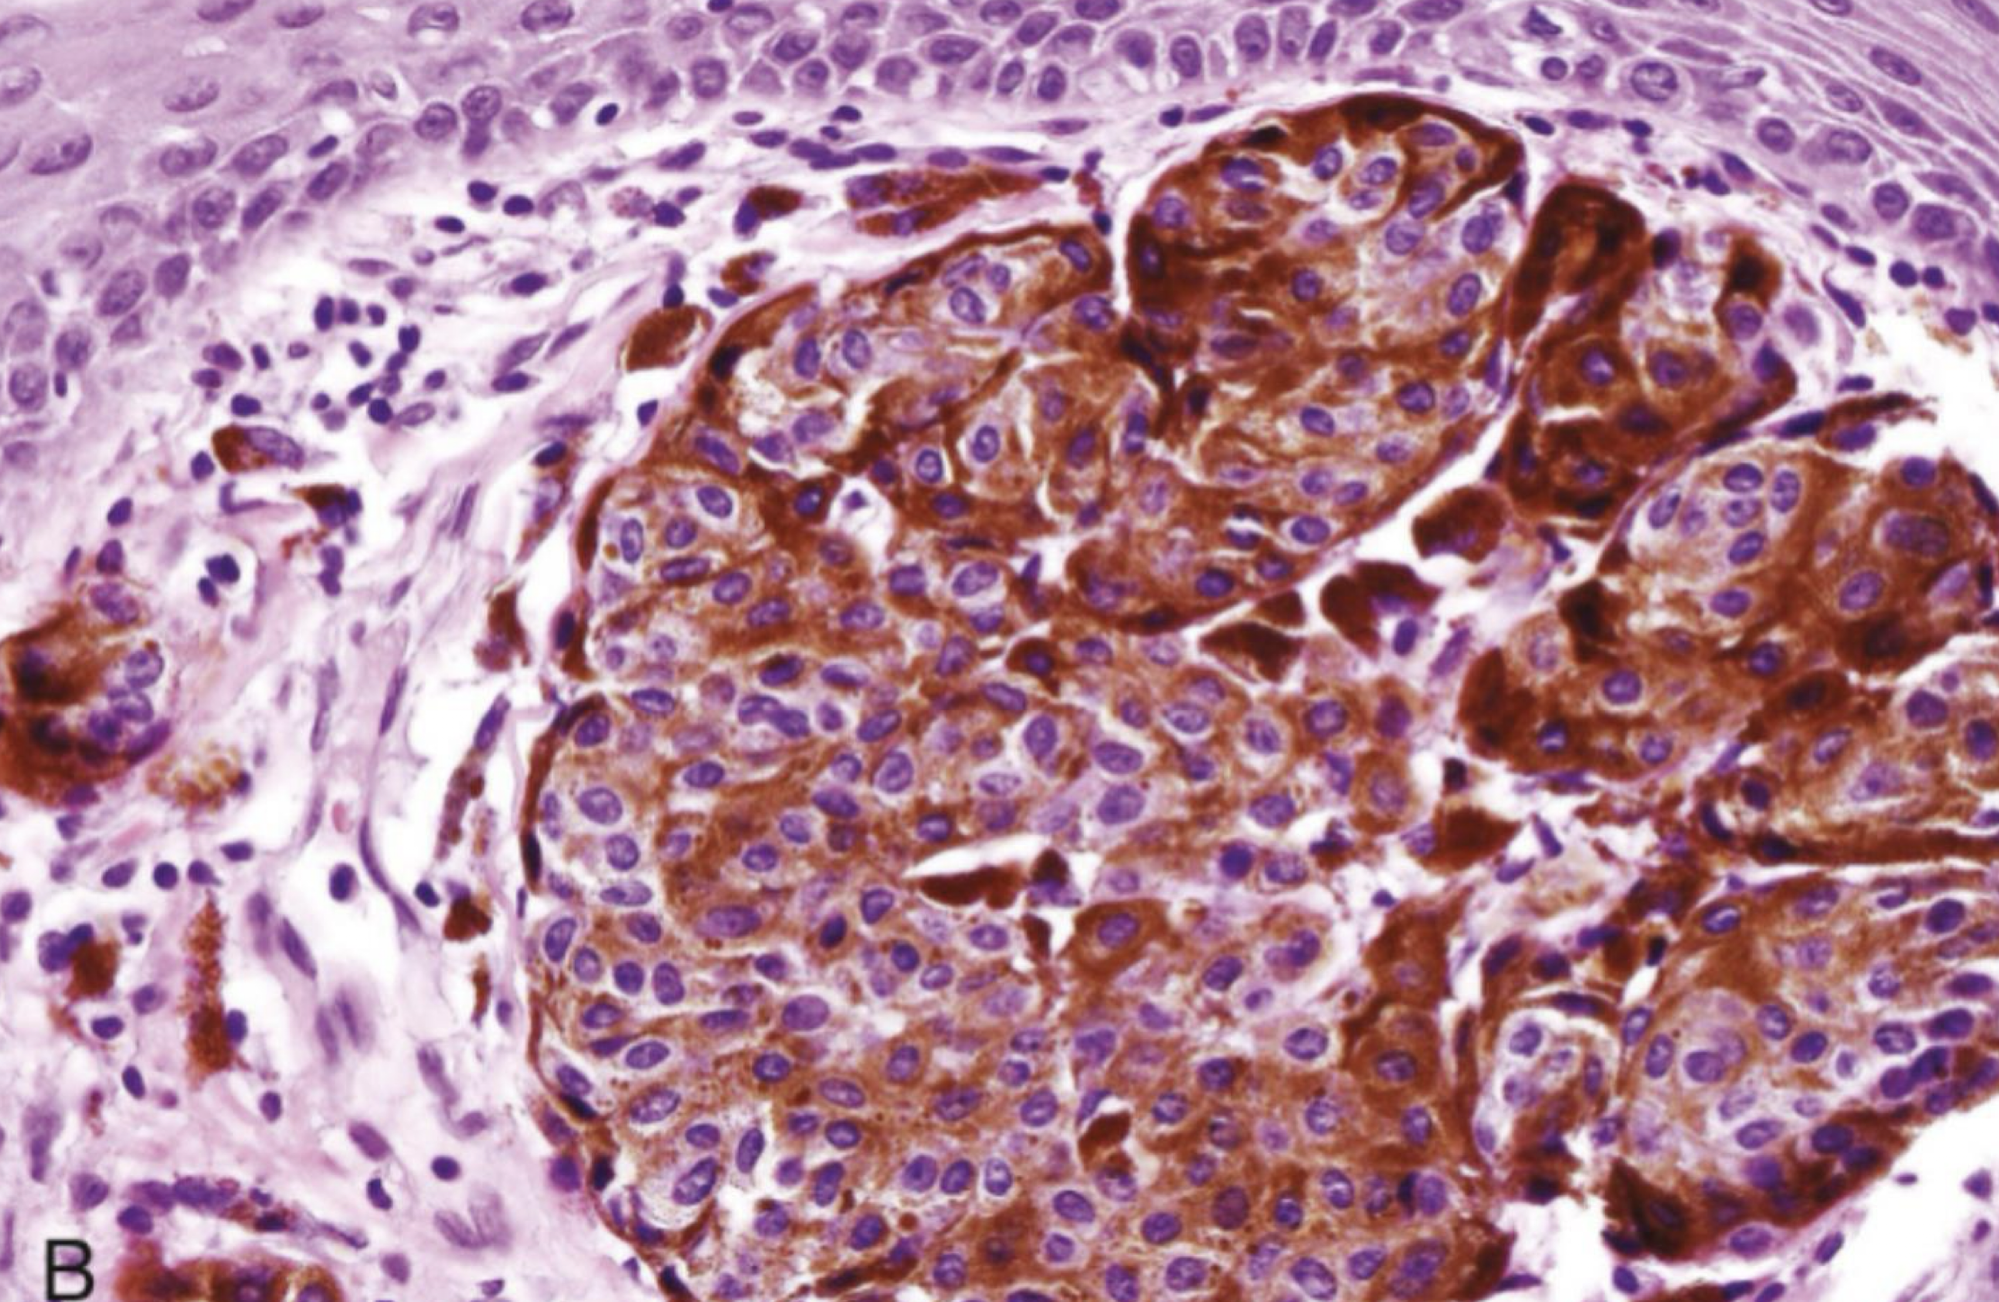

which premalignant/malignant melanin-associated pigmented lesion?

More prevalent in African Americans and Japanese

Arise de novo

7th decade, slight male predilection

Palatal mucosa, maxillary gingiva (>70%)

Breslow and Clark criteria (skin criteria) do not correlate with clinical behavior/prognosis

can be heterogenous or homogenous

oral melanomas

KIT gene mutation

oral mucosal melanoma

heterogenous oral melanoma

oral melanoma